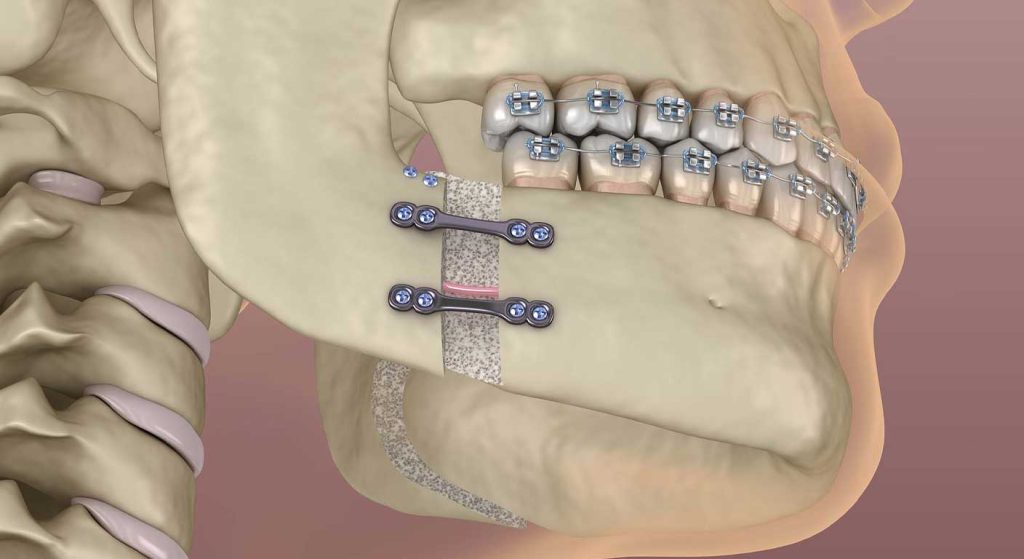

◦ انجام جراحی: جراحی در بیمارستان و تحت بیهوشی کامل انجام می شود. جراح با ایجاد برش هایی از داخل دهان، استخوان های فک را جابجا کرده و در موقعیت جدید با صفحات و پیچ های کوچک تیتانیومی ثابت می کند.